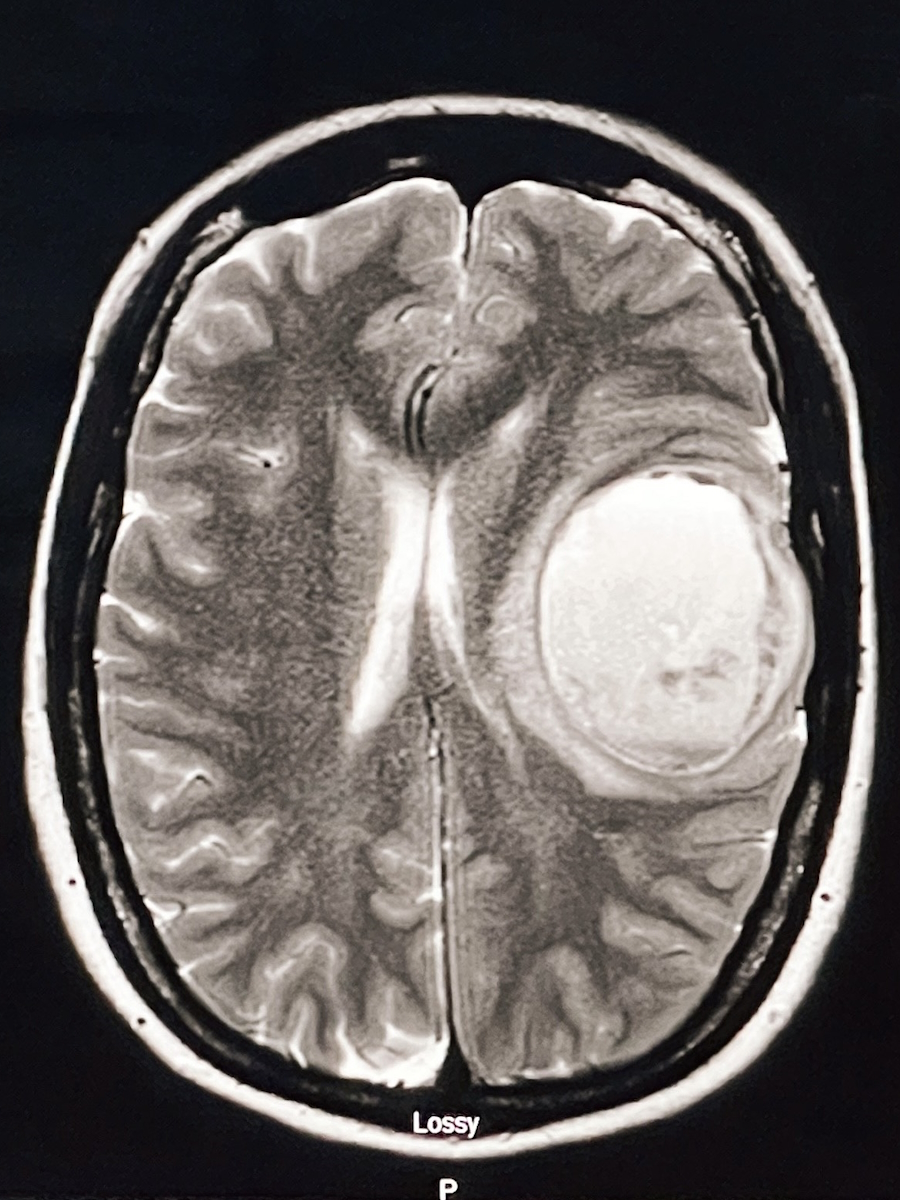

Alarmed, she went home and searched “brain tumor while pregnant,” a phrase no expectant parent ever wants to type. An emergency room visit and MRI revealed a large mass on her language center, but because she was pregnant, her team could not yet fully characterize what they were seeing.

One of the residents came and he was excited. He said they found a mass on my language center. I was excited at first because it felt like validation that it wasn’t me having a mishap. It was a big mass right on my language center. But they didn’t know what it was. Is it a brain bleed? Is it a stroke? Is it a tumor? They couldn’t do an MRI with contrast since I was pregnant.

I stayed in the ICU for a couple of days. While they tried to decide whether they could do an awake craniotomy to see if they could do a biopsy, the problem was that they were afraid that the blood had already coagulated inside my brain and they would not be able to get a good sample.

I was doing speech therapy and feeling good for a couple of days, but then it started going downhill quickly. My husband took me back to the hospital a few days later and the mass had nearly doubled in size.